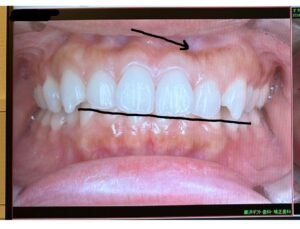

写真の黒い線は、上下の歯が噛み合う位置、**咬合平面(こうごうへいめん)**を示しています。

矯正前はこのラインがやや斜めでしたが、治療によって左右の歯の高さが整い、まっすぐに近づいてきています。

この変化は、個人的に一番感動したポイントです。

咬合平面とは、歯がかみ合う高さやラインのことです。前歯から奥歯まで、かみ合わせたときにだいたい一直線になる“かみ合わせのバランス”このラインが傾いていると、口元が左右非対称に見えたり、噛み合わせに負担がかかることがあります。

マウスピース矯正では、歯の高さを細かく調整することで、この咬合平面を整えていきます。